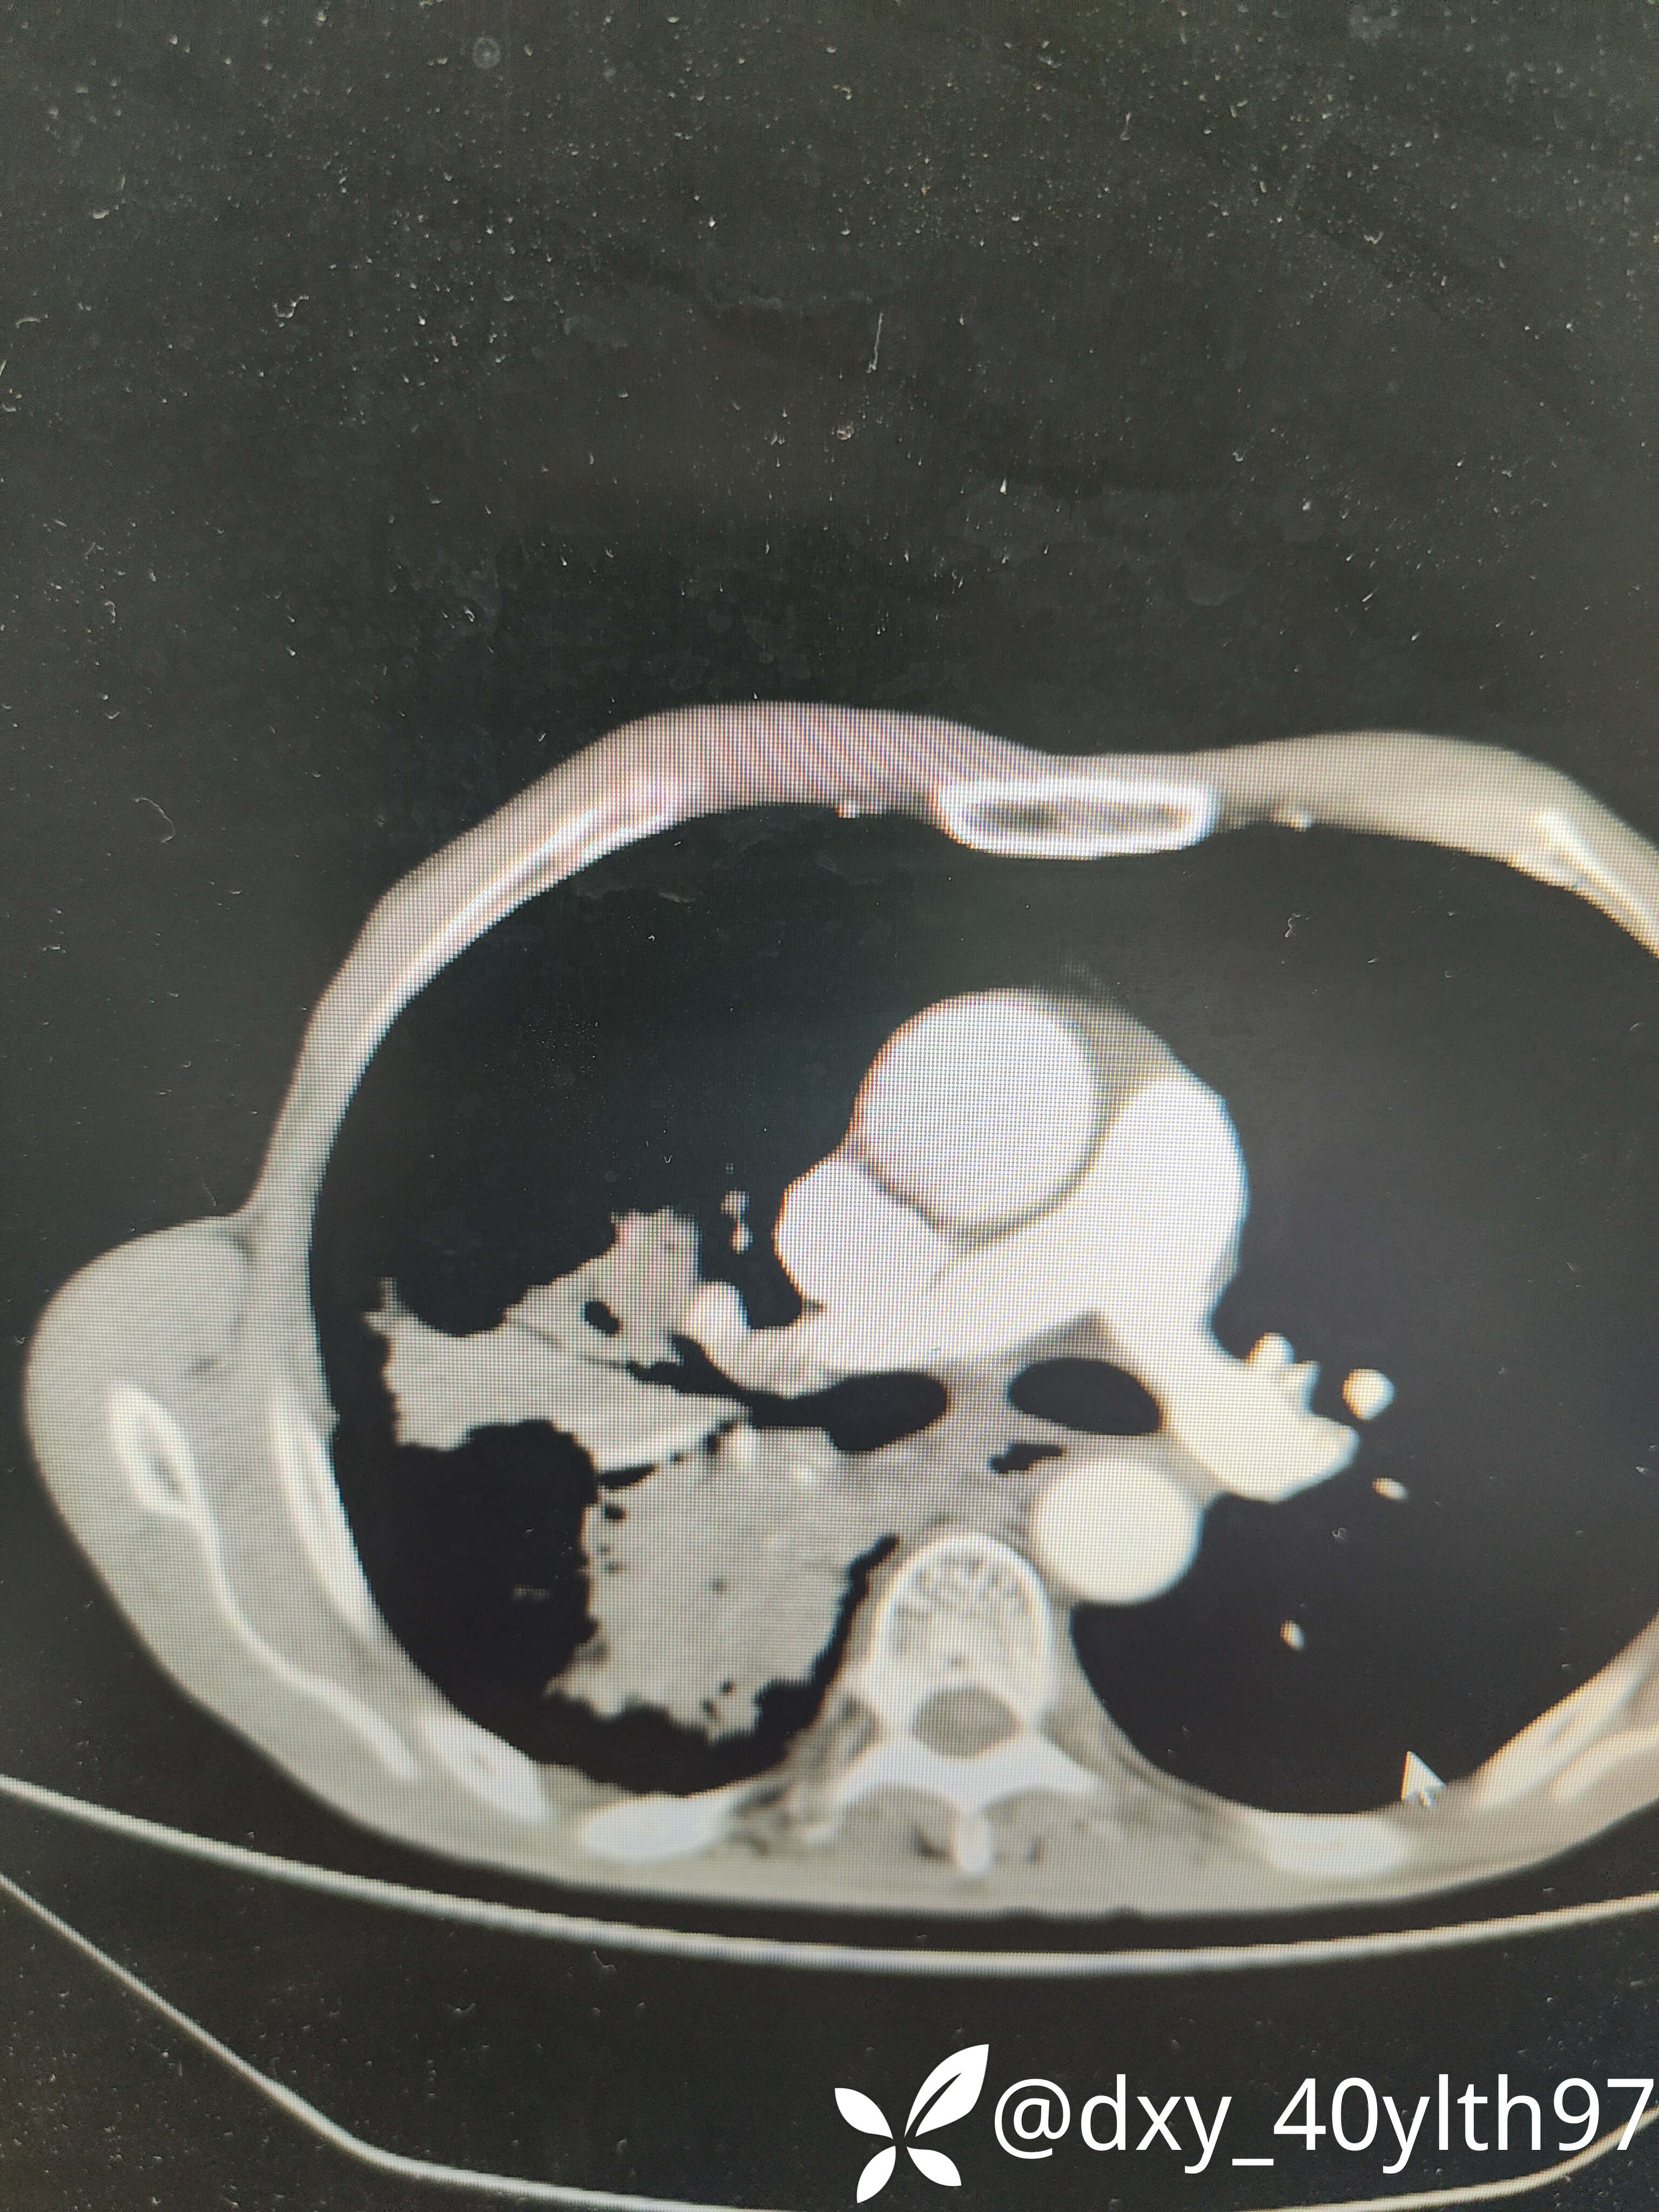

肺部CT平扫+增强提示肿瘤?

治疗经过:2023-8月入院后查肺部CT平扫

2023年8月肺部CT平扫影像结果提示:1.右肺上叶密度增高影较前显著增大,建议进一步检查;2.两肺多发斑片结节灶较前增多,部分增大。

肺部增强CT影像学提示:右肺内大片不规则影轻度强化,肿瘤可能。